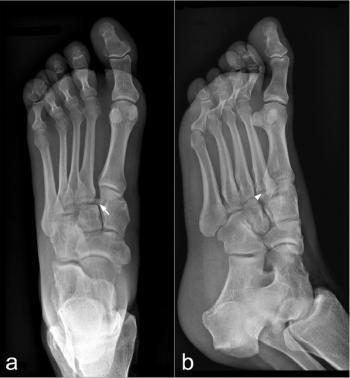

The study, involving 500 patients, showed that artificial intelligence (AI) assistance enhanced fracture diagnosis on radiographs and reduced reading time for radiologists of varying experience levels.